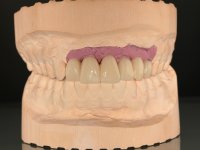

O paciente foi observado conjuntamente e a dúvida que surgiu de imediato foi se seria possível com a regeneração óssea a efectuar poder ser reabilitada naturalmente a zona das papilas interdentárias. Nesse sentido foi feito um enceramento de diagnóstico que contemplaria as duas hipóteses, utilizando ou não a cerâmica gengival. A confecção desse enceramento foi fundamental para expor ao paciente a dificuldade da reabilitação. O wax-up deu origem a um mock-up que foi aprovado pelo paciente e que simultaneamente serviu de guia imagiológica. O caso foi planificado cirurgicamente e realizada uma guia cirúrgica com que foram colocados os implantes. Após 10 semanas foi feita a 1ª impressão para confecção da ponte provisória. Foram criados os primeiros perfis de emergência na gengiva artificial e foi digitalizado o modelo. Por processo de CAD-CAM foi confeccionada uma ponte provisória aparafusada baseada no enceramento de diagnóstico. A ponte trabalhou durante 8 semanas os tecidos moles que foram fielmente copiados numa impressão com técnica de moldeira aberta. Os transferes foram individualizados com resina composta para copiarem fielmente os perfis de emergência criados pela ponte provisória. Confeccionado o modelo de trabalho definitivo, foi realizada uma infra-estrutura em zircónio seguindo a orientação do enceramento de diagnóstico. O assentamento da infra-estrutura foi testado em boca e simultaneamente foi novamente impressionados os tecidos moles com um silicone fluido. Nessa consulta foi feito o levantamento da cor. Os dentes 13 e 23 apresentavam uma saturação anormalmente forte que resolvemos não valorizar, optando por privilegiar a relação com o sector antero-inferior. Foi realizada uma nova gengiva artificial com a impressão que acompanhou a impressão de arrasto com a infra-estrutura. Após a colocação da cerâmica na infra-estrutura foram coladas as meso-estruturas. O trabalho final foi aparafusado lentamente permitindo a adaptação dos tecidos moles.